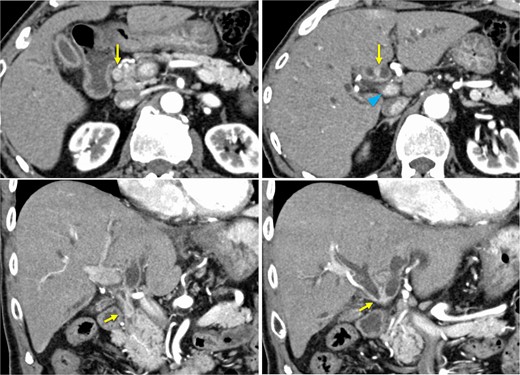

A 76-year-old man was referred to our hospital due to fatigue, upper abdominal discomfort, and jaundice. He had no appreciable medical history. Multidetector row computed tomography revealed hilar bile duct thickening and intrahepatic bile duct dilation, suggestive of pCCA (Fig. 1).

Preoperative contrast-enhanced computed tomography. Hilar bile duct thickening (arrows) and intrahepatic bile duct dilation are observed. The portal vein (arrowhead) is close to the thickened hilar bile duct.